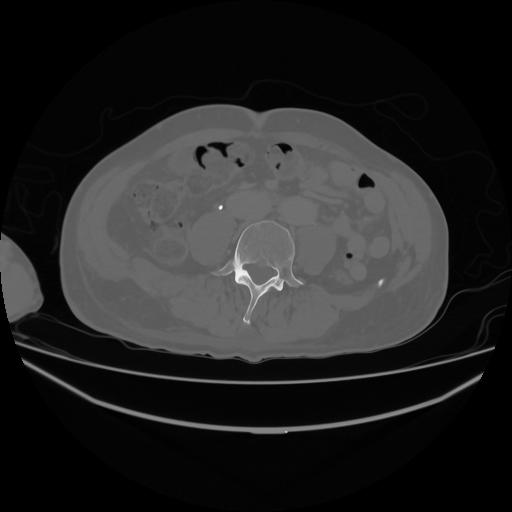

5 CUERPO,CE,Vol,1.0,CUERPO,,